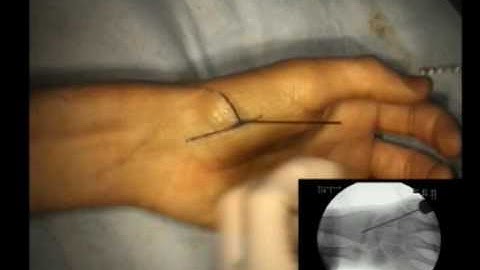

Technique of percutaneous fixation of scaphoid with headless compression screw @bipinhandsurgeon